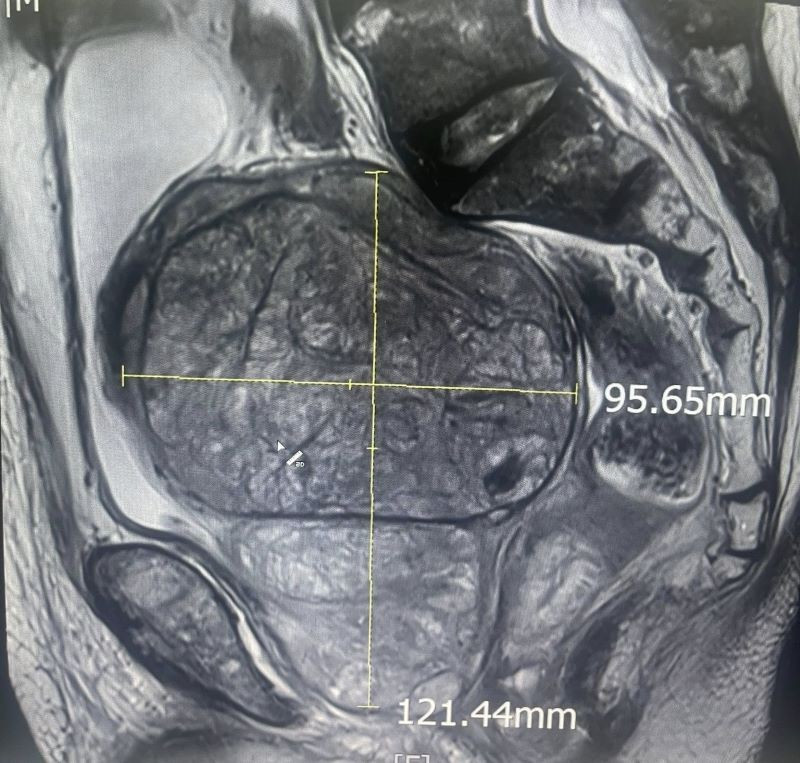

Khối u có kích thước khổng lồ trên phim chụp - Ảnh BVCC

Kích thước khối u khổng lồ trên phim chụp - Ảnh BVCC